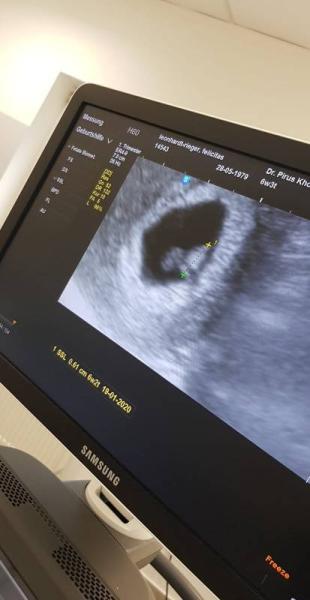

Heute durfte ich meinen Zwerg endlich sehen zwar noch ganz mini mini klein aber das schlägt bereits. Soooo schön Was ich nur total doof finde....in meiner letzten Schwangerschaft habe ich ein Ultraschallabo gebucht. Nichz weil ich übervorsichtig bin. Sondern weil ich es so schön finde die Entwicklung zu sehen. Jetzt sagten die mir, dass die das durch diese neue Datenschutzverordnung nicht mehr dürften habt ihr davon auch schon gehört?

Glückwunsch, ich war auch total glücklich heute vorallem das Herzchen schlagen zu sehen Wie groß ist dein zwerg?

Mein zwergizwerg ist 3.4mm Keine Ahnung was das mit dem Datenschutz zu tun hat. Da gibt es aufjedenfall ein neues Gesetz sagte die Helferin. Völliger Blödsinn. Hatte mich so gefreut. Naja freue mich jetzt erst auf eine schöne Kugelzeit

Huhu, freut mich, dass du dich so über das Bild freust und alles ok ist. Ich war am Dienstag bei 6+3 und auch da war alles gut. Herzaktionen waren auch zu sehen. Dabei habe ich das Igel Angebot angesprochen. Alle 4 Wochen Ultraschall und andere Dinge für 190 Euro. Davon übernimmt 100 die Kasse. Also da verstehe ich deinen Arzt nicht